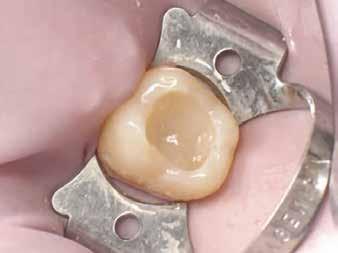

A restauráció polírozását korongok és szilikonpolírozók kombinációjával végezte, majd az okklúzió ellenőrzését követően a pácienst a rendelőből otthonába bocsátották. Megjegyzendő, hogy a finírozást követően az eredeti okkluzális anatómia csak minimális mértékben módosult (17. ábra).

Egy 26 éves páciens a jobb felső első molárisának ideiglenes, endodonciai kezelést követő, I. osztályú restaurációjával jelentkezett. Mivel a fogban jelentős mennyiségű dentin és zománc volt jelen, valamint a marginális peremek épek voltak, a páciens tájékoztatása és beleegyezése után a kezelési terv a direkt kompozit restauráció volt (18. ábra). A fog preparálása az 1. esetben leírtak szerint történt (19. ábra).

Végül a szerző az üreget a „Modified Super-Closed Sandwich Approach” [20] technikával állította helyre (amely a klasszikus rezin-módosított üvegionomer zárt-szendvics technika módosított változata), és az okkluzális iránytű módszerét alkalmazta a rágófelszín lezárására (20. ábra).